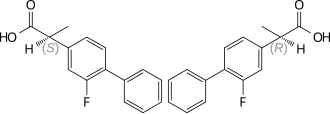

| Other names | (±)-2-fluoro-α-methyl-(1,1'-biphenyl)-4-acetic acid |

| Formula | C15H13FO2 |

| Chirality | Racemic mixture |